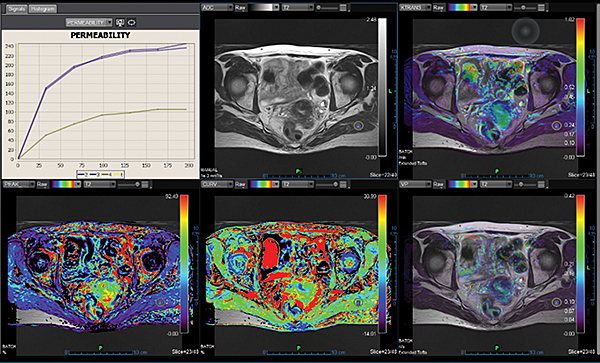

Додаток Prostate Streamlined.

Спеціальні програми Olea SphereTM для аналізу передміхурової залози включають в себе розширені можливості для оцінки дифузії та якісної оцінки перфузії. Також пропонують ефективний мультипараметричний аналіз усіх доступних послідовностей для візуалізації простати. В додатках реалізовано аналіз кінетики та кількісних даних на основі надійних математичних моделей. Програми передміхурової залози включають звіт PI-RADS® 2 для покращення виявлення, характеристики та вірогідності встановлення діагнозу раку простати. Цей програмний пакет стандартизує виклад протоколів опису, а також вказує рівень підозри або ризик виникнення клінічно значущих пухлин.

Додаток MR Prostate

Додаток MR Prostate інтегровано до розширеної візуалізації Vitrea. Він забезпечує виявлення, характеристику та стадіювання ураження.

Забезпечує миттєву комплексну оцінку ураження та високоякісну оцінку дифузії

Дає змістовну звітність, включаючи локалізацію та об’єм ураження

Надає рекомендації PI-RADS V2 щодо стандартизації термінології і протоколу опису, а також уточнює ризик клінічно значущих пухлин